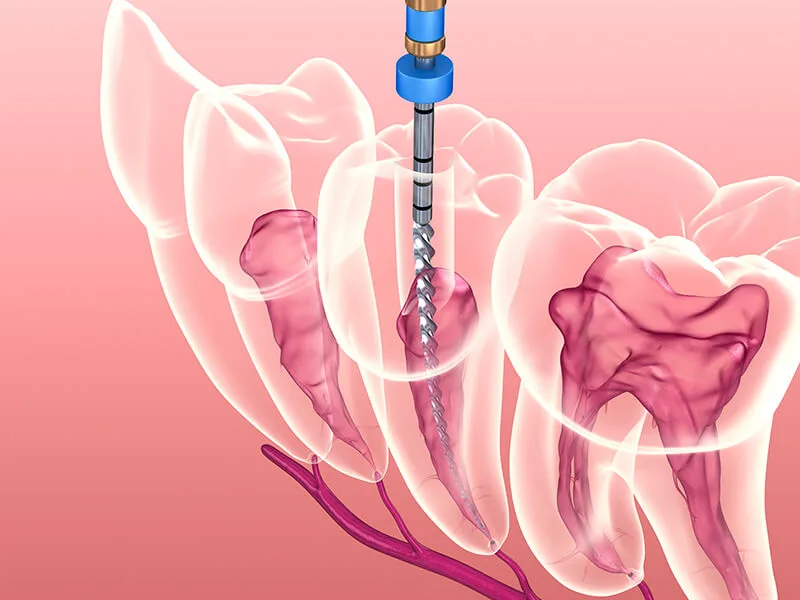

A endodontia envolve a limpeza e desinfecção dos canais radiculares.

Após essa etapa, o dente é obturado com materiais biocompatíveis.

O tratamento de endodontia é realizado em várias etapas.

Inicialmente, o dentista realiza um exame clínico e radiográfico.

Isso ajuda a identificar a extensão do problema.

Após o diagnóstico, o dentista anestesia a área afetada.

Em seguida, ele faz uma abertura no dente para acessar os canais radiculares.

A limpeza é feita com instrumentos específicos, assegurando a remoção de tecidos infectados.

Por fim, os canais são obturados e o dente é restaurado.

Esse procedimento é realizado com tecnologia moderna, assegurando segurança e eficácia.